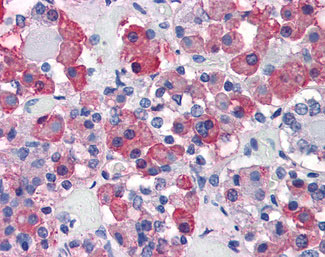

Anti-Growth Hormone antibody IHC of human anterior pituitary. |